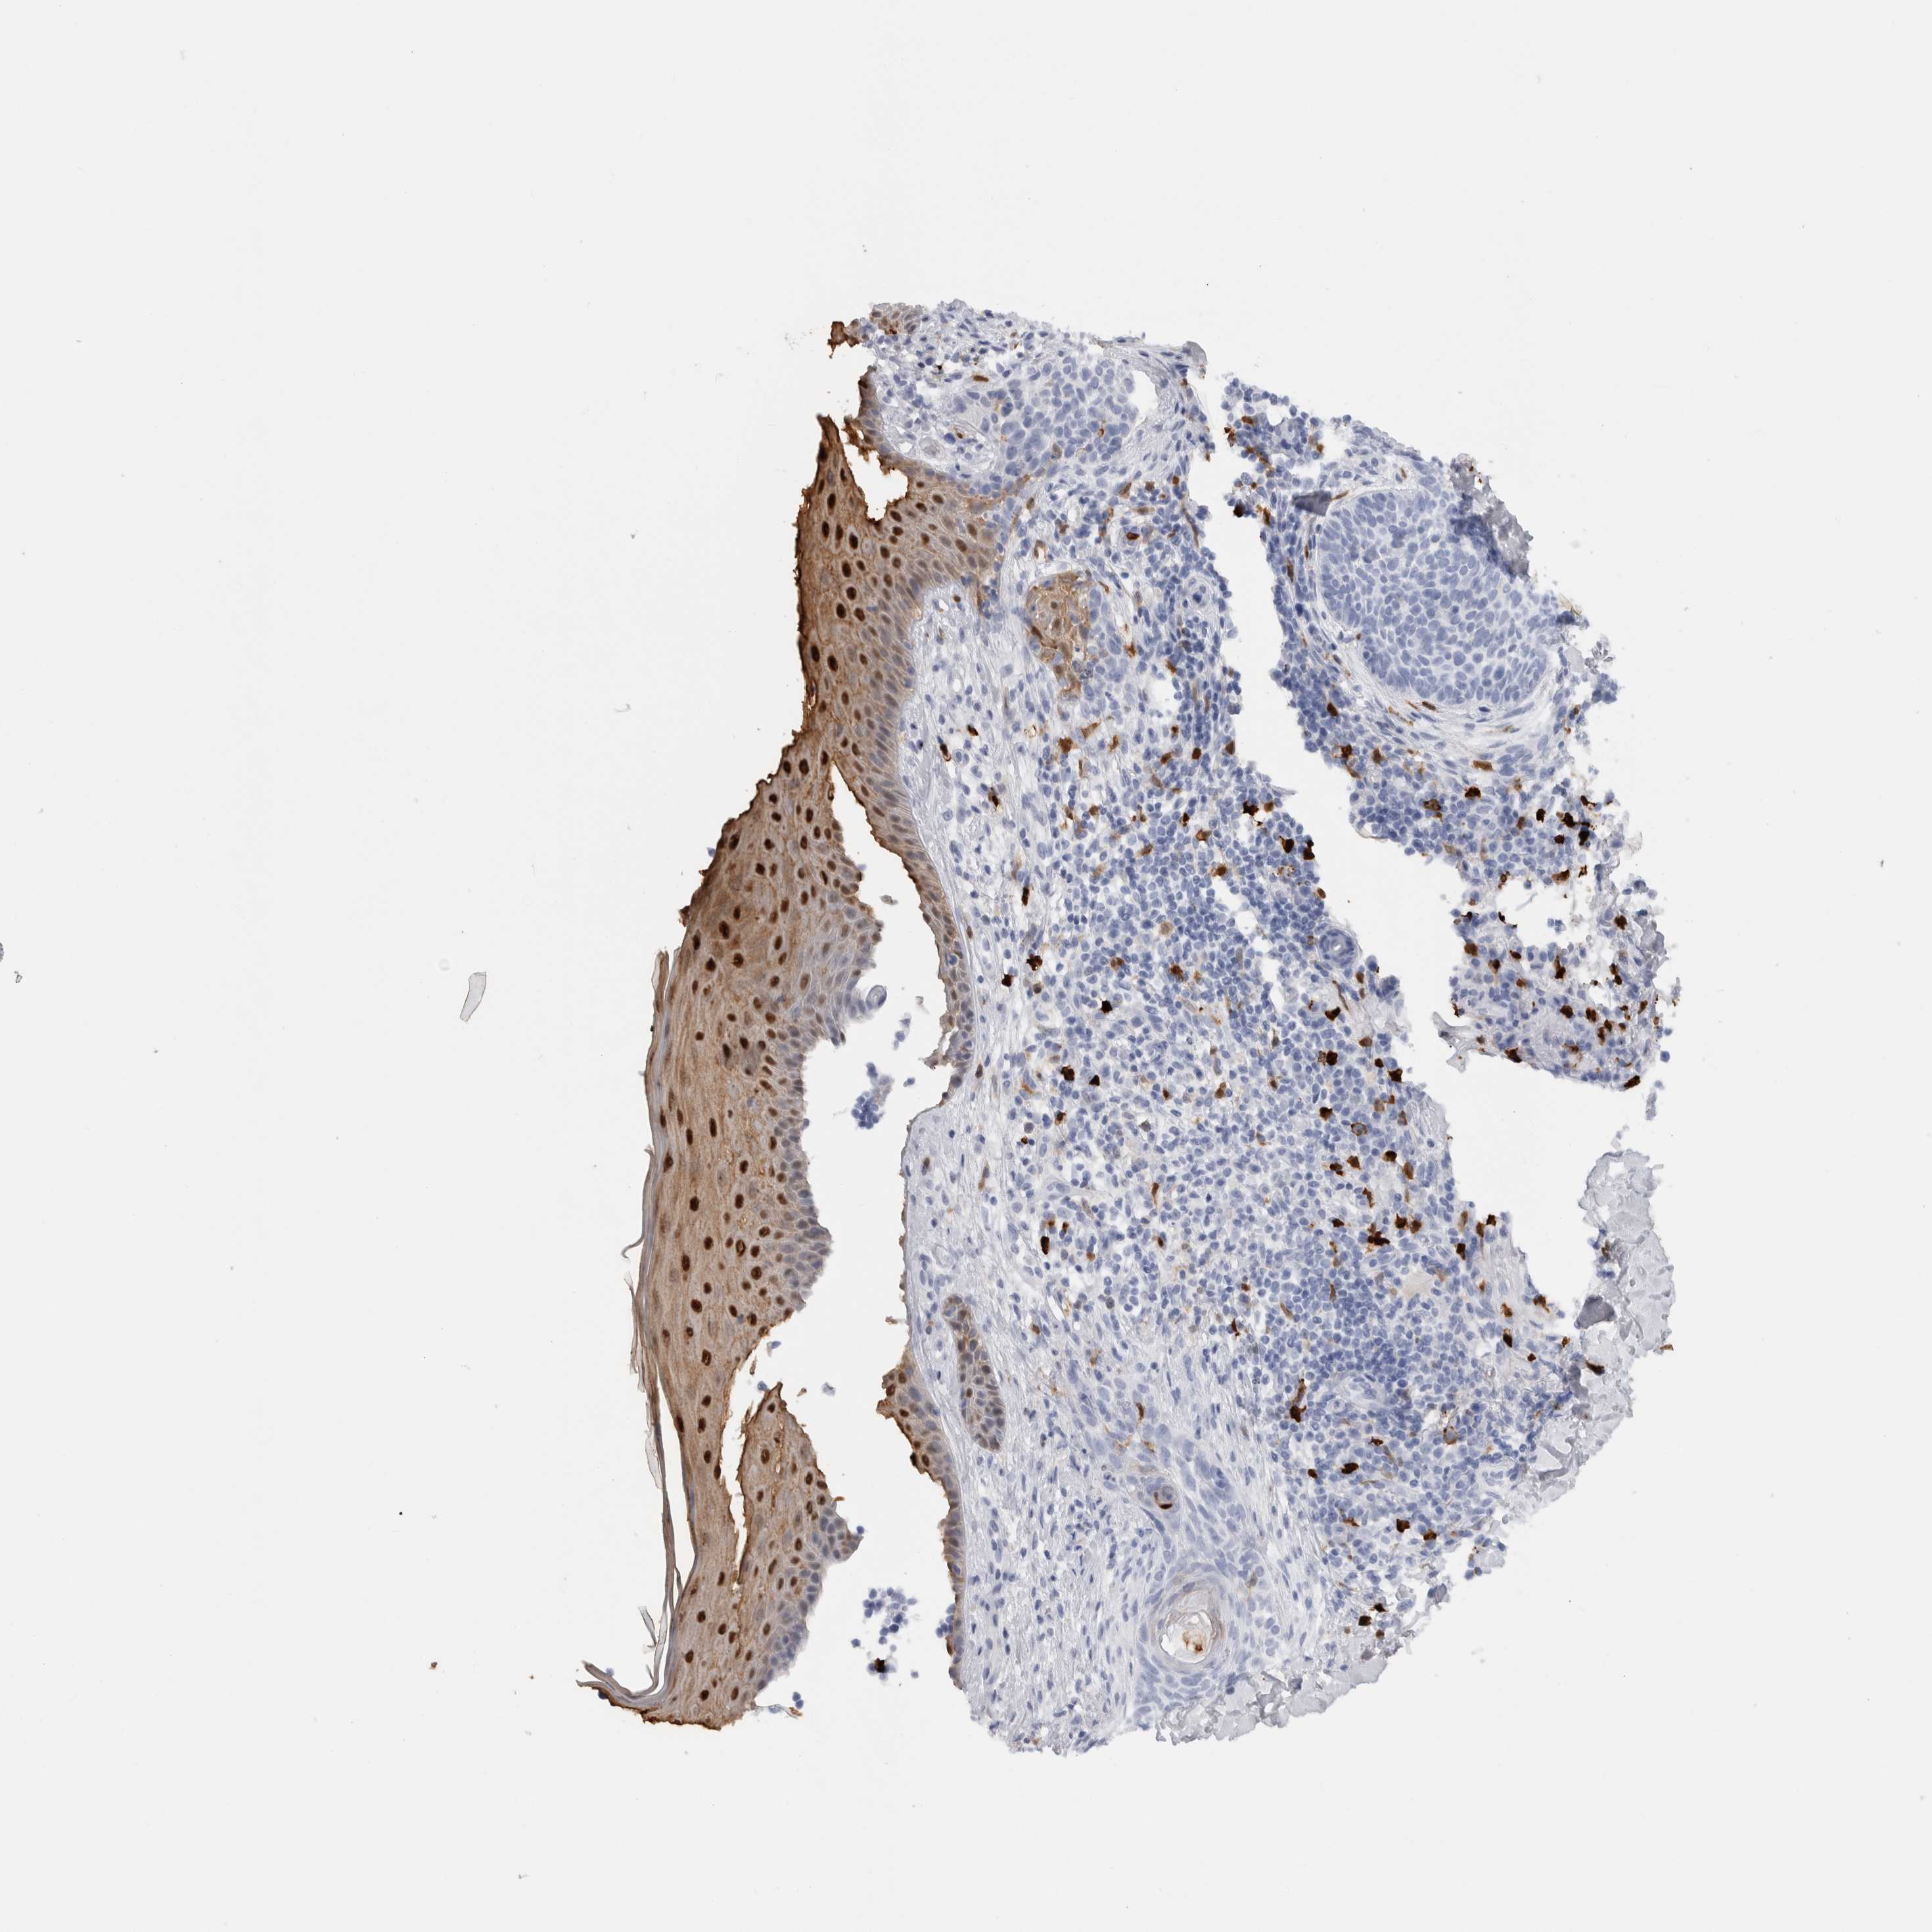

CANCER SKIN CANCER Show tissue menu

Basal cell and squamous cell cancer

SKIN CANCER - Protein expressioni

A mouse-over function shows sample information and annotation data. Click on an image to view it in a full screen mode. Samples can be filtered based on level of antibody staining by selecting one or several of the following categories: high, medium, low and not detected. The assay and annotation is described here.

Each image is clickable and will lead to virtual microscopy that enables deeper exploration of all samples and also displays staining intensity scores, fraction scores and subcellular localization as well as patient and tissue information for each sample.

Antibody HPA024372

Antibody CAB002791

Basal cell carcinoma

Squamous cell carcinoma, NOS

Squamous cell carcinoma, metastatic, NOS